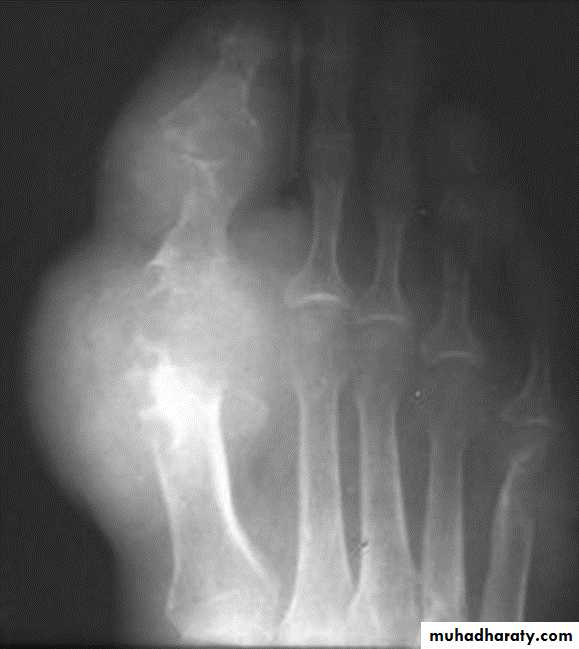

GOUT

Heterogeneous group of entities characterized by recurrent attacks of arthritis secondary to deposition of sodium urate crystals in and around joints.

Radiographic features:

Lower extremity > upper extremity; small joints > large joints

* First MTP is most common site

* Marginal, peri articular erosions: overhanging edge

* Erosions may have sclerotic borders

* Joint space is preserved

* Soft tissue and bursa deposition

Tophi: juxtaarticular, helix of ear

* Erosions and tophi only seen in longstanding disease

* Tophi calcification, 50%